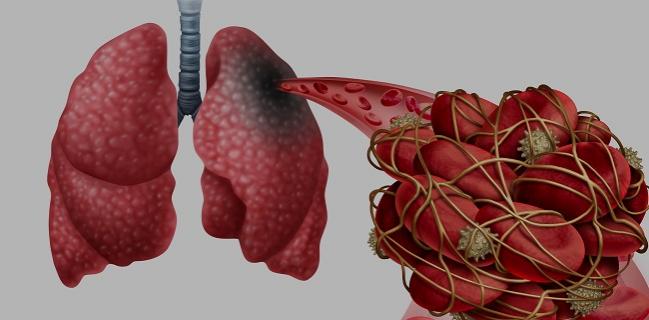

Blood Vessels In Lungs Split In Response To Covid 19

Pulmonary Vascular Endothelialitis Thrombosis And Angiogenesis In Covid 19 Nejm

Immune Mechanisms Of Pulmonary Intravascular Coagulopathy In Covid 19 Pneumonia The Lancet Rheumatology

Blood Clotting Patterns In Lungs Of Covid 19 Patients May Help Explain Apparent Differences In Mortality